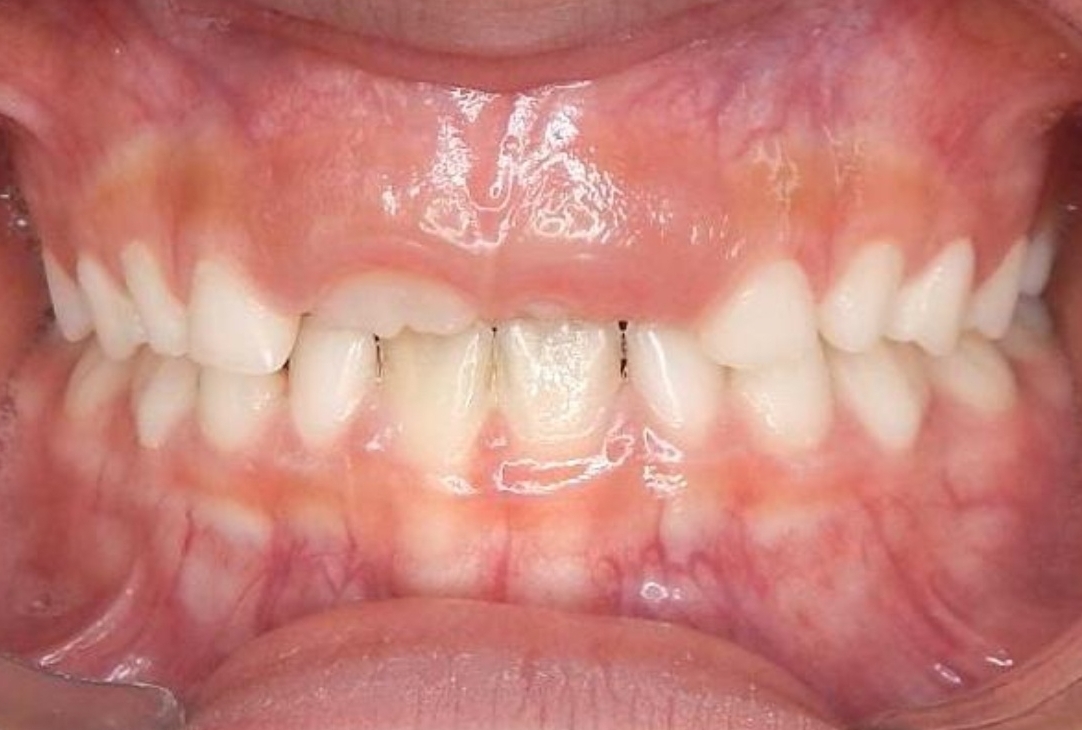

ORTODONTIA MIOFUNCIONAL

J.N.E.